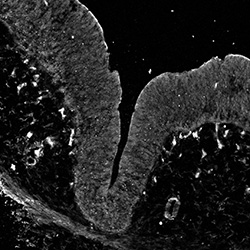

DAPI

6PCW human midbrain